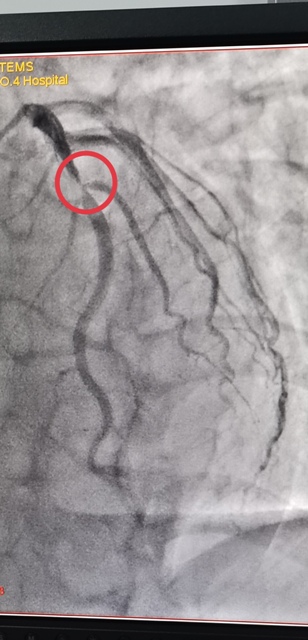

45岁的郭先生,一周前无明显诱因出现胸前区疼痛,伴有胸闷、心悸,疼痛发作时间持续10分钟后自行缓解,伴有大汗淋漓,来六合彩生肖心血管内科就诊诊断为“冠心病不稳定性心绞痛”,于2021年1月3日早上10点进入导管室,实施了冠脉造影术 经皮冠状动脉内支架植入术,心内科主任王选琦主任医师介绍说,这是省四院第一例648元支架手术,手术进展顺利,患者术中、术后无不适症状,术后病症明显缓解,目前在心内科治疗观察。

陕西省第四人民医院于2021年1月1日零时执行国家组织冠脉支架集中带量采购中选结果,据悉,中选的冠脉支架产品的平均价格由原来的7500元降至648元。为确保患者在2021年1月1日当天能够使用中选产品,陕西省第四人民医院迅速贯彻省市医保局要求,已经将中选支架采购安排到位,从2021年1月1日0时开始实施新的价格标准。郭先生是蓝田人,成为新年第一个享受国家医改福利的人。